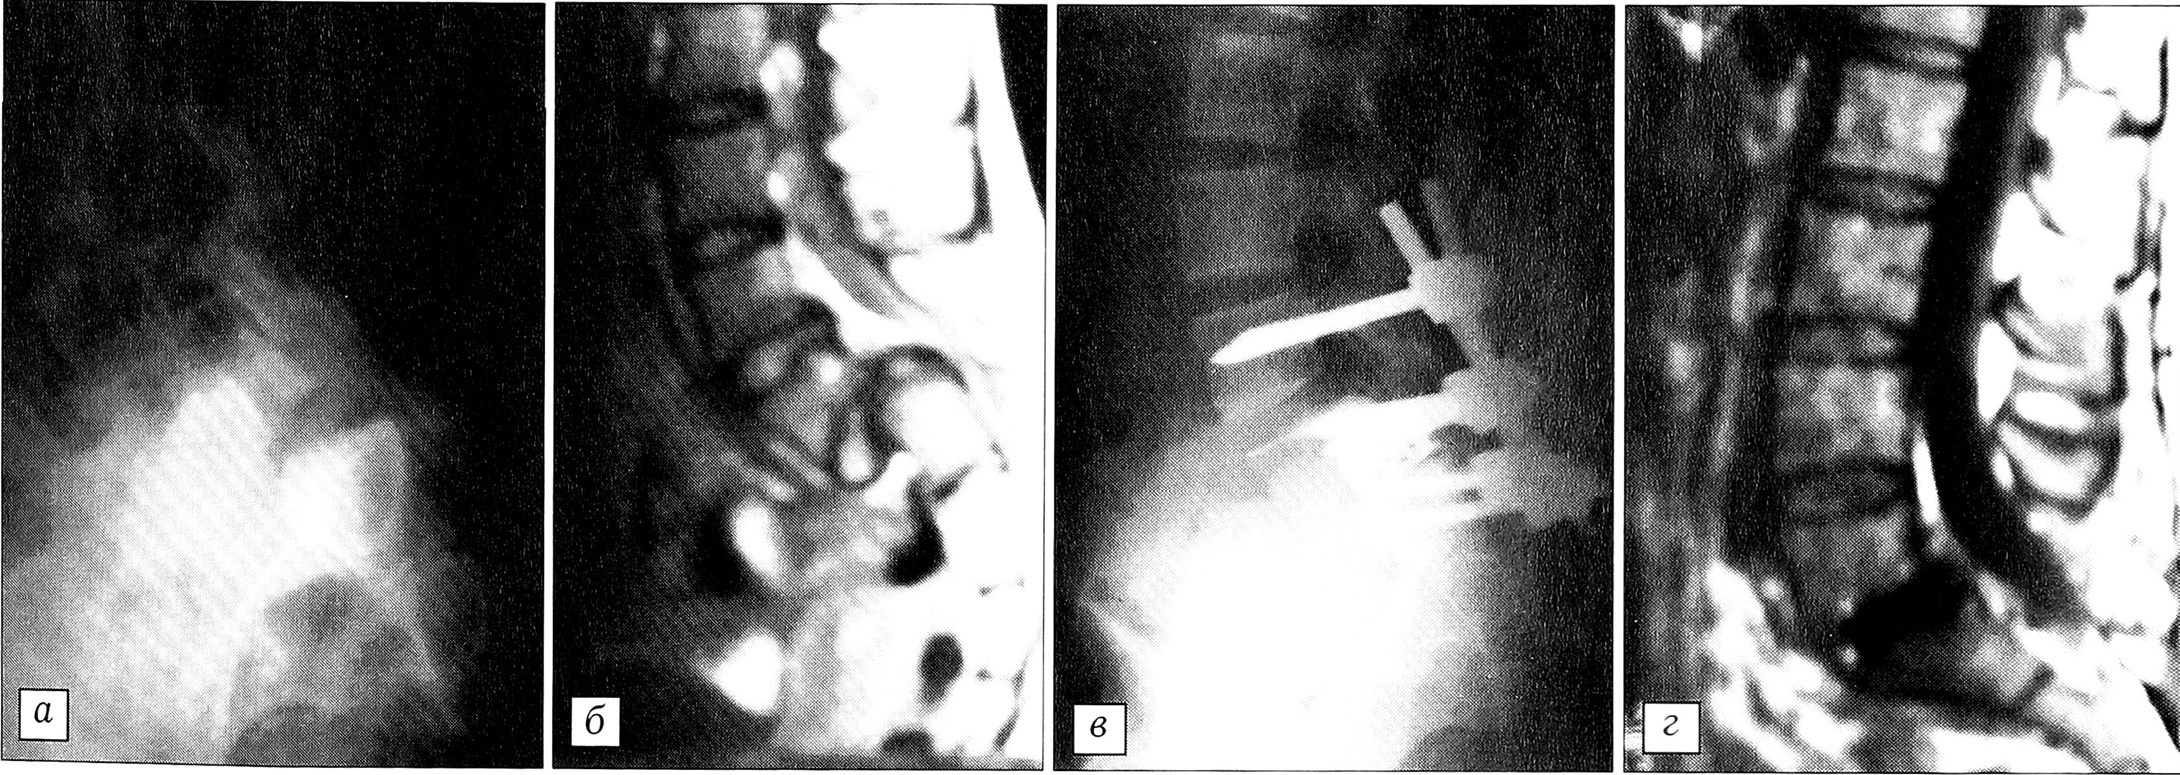

Отдельный вопрос — микрохирургическая дискэктомия при спондилолистезе. Если передний доступ при этой патологии достаточно отработан [2], то в хирургическом лечении задним доступом остается много спорных вопросов. W. Caspar считал, что микродоступ при спондилолистезе противопоказан как трудно выполнимый и приводящий к увеличению смещения. Однако при применении транспедикулярных фиксаторов и межпозвонковых кейджей, имплантируемых из междужкового доступа, мы сочли возможным отказаться от ламинэктомии на одном или даже двух уровнях и использовали малоинвазивные доступы с каждой стороны и на разных уровнях (рис. 4). Такая методика избавляет пациента от вторичной компрессии содержимого позвоночного канала эпидуральным рубцом, образующимся в отдаленные сроки после ламинэктомии.

Рис. 4. Больная И. 14 лет. Диагноз: спондилоптоз L5.а — рентгенограмма до операции;б — магнитно-резонансная томограмма до операции;в — рентгенограмма после операции;г — магнитно-резонансная томограмма после операции: произведены микродискэктомия L5-S1 и спондилодез с транспедикулярной фиксацией.